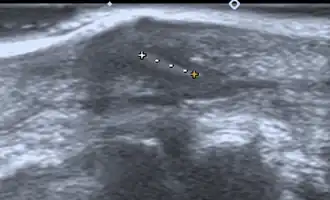

Ultrasonography of a subcutaneous splinter (in a finger) 4 x 1mm with oblique stroke.

If manual detection and localization fail, the main methods for medical imaging of splinters are:

• Medical ultrasonography – used to locate glass, metal, pencil graphite, some plastics, stone, and some types of wood.[6]

Small wooden splinters (1–4 mm) distant from bones are most easily detected by ultrasonography, while CT scan and magnetic resonance imaging have higher sensitivity for those near bones.[7]